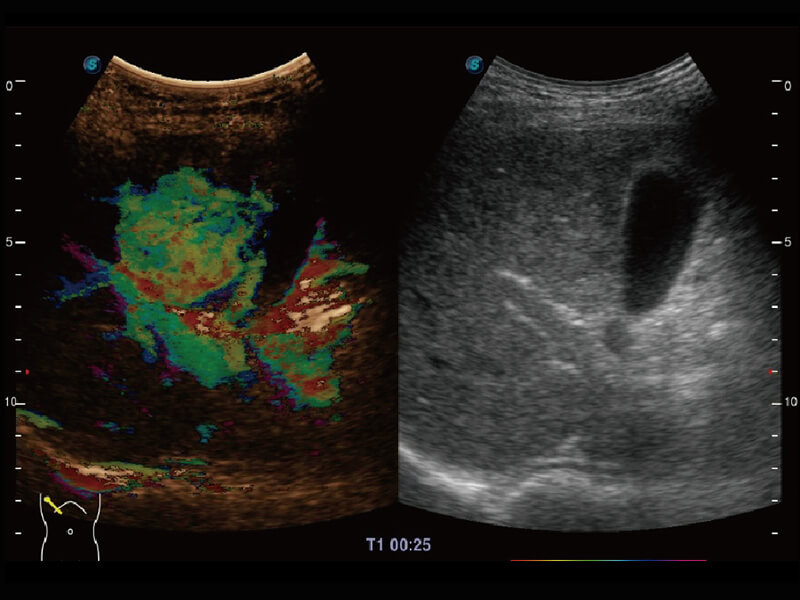

S60创新的探头工艺、高精度模数转换系统、前沿的波束重建技术,从前端信号处理每一个环节采集无损声学数据,真实还原组织原貌,再现解剖细节。

创新的超宽频带技术,为容积成像带来优质的二维图像基础,为您呈现更丰富的结构细节,栩栩如生地展示宝宝的宫内形态以及各种组织的立体结构。